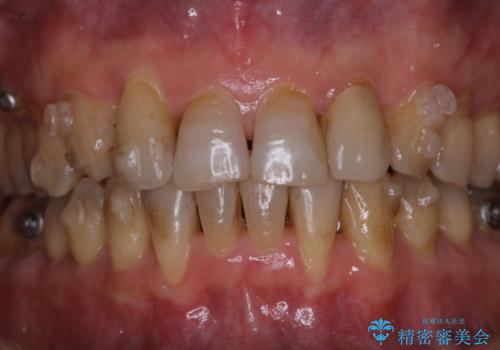

- マウスピース矯正中(インビザライン)に着色落としをしたいとのことでした。PMTC60分コースを行いました。

PMTC(保険外治療)は、毎日の歯磨きで落としきれない汚れや、コーヒ、紅茶・タバコのヤニなどの着色も除去します。目には見えない歯と歯の間・歯肉の境目・インビザライン中はアタッチメント周囲などに残っているプラーク(歯垢)もしっかり取り除きます。PMTCでは専門的な機械や材料を使用して、徹底的に汚れを除去するため、虫歯・歯周病・口臭予防などにつながります。

またPMTCを行うことで、ご自身本来の歯の色になり自然な明るさになります。